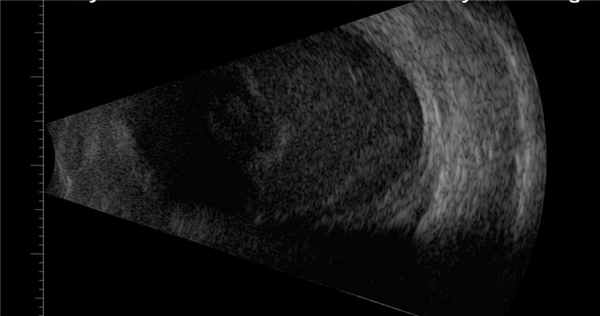

В-сканирование. Экссудат в стекловидном теле.

При дополнительном ультразвуковом исследовании глаза определяют отек оболочек и помутнения различной выраженности в стекловидном теле – признаки активного воспалительного процесса.

- УЗИ глаза. Выявляет ограниченные или тотальные помутнения в стекловидном теле. Для верификации возбудителя проводится посев культуры из стекловидного тела и водянистой влаги.